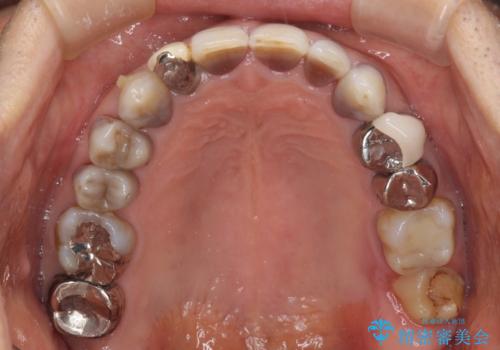

- 前歯のクロスバイトを気にして来院された患者様です。

骨格的に下顎が前方位ではありますが、歯並びが改善されれば正常咬合となることが分かったため、インビザラインを用いて咬み合わせを改善していくこととしました。